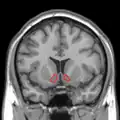

Dopamine and serotonin- MRI coronal slice showing nucleus accumbens outlined in red

Nucleus accumbens highlighted in green on coronal T1 MRI images